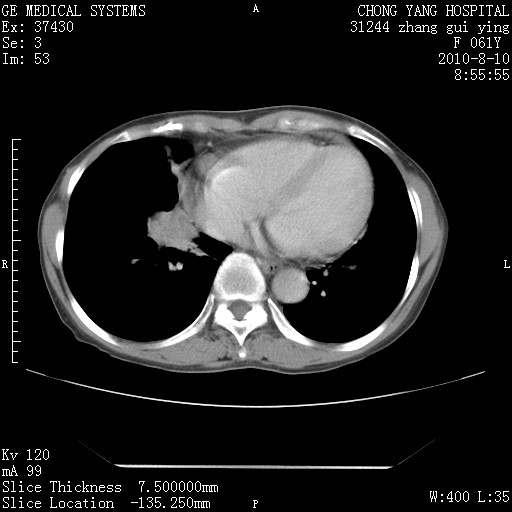

标题: CT28314:F61Y胸部增强,发热咳嗽一周入院,后面的为一周前平 [打印本页]

标题: CT28314:F61Y胸部增强,发热咳嗽一周入院,后面的为一周前平

1、支持考虑右侧中央型肺癌伴右肺中叶节段性不张及下叶支气管黏液痰栓    2、左肺上叶舌段感染。

支持3楼意见,还要考虑:纵隔及肺门淋巴结转移、右侧少量胸腔积液。

确切的说:1:右肺下叶中心型肺癌侵及中叶支气管并中叶不张,纵膈淋巴结转移。2:左肺舌叶炎症。3:右侧胸腔少量积液

块影平扫32hu,动静脉期62-70hu.

1:右肺下叶中心型肺癌侵及中叶支气管并中叶不张,纵膈淋巴结转移。2:左肺舌叶炎症。3:右侧胸腔少量积液。支持!

右肺下叶内基底段近膈不规则肿块,考虑右肺下叶周围型肺癌可能性大。

考虑右下肺肺癌,纵隔淋巴结转移i。

右肺下叶中心型肺癌侵及中叶支气管并中叶不张,纵膈淋巴结转移。2:左肺舌叶炎症。3:右侧胸腔少量积液